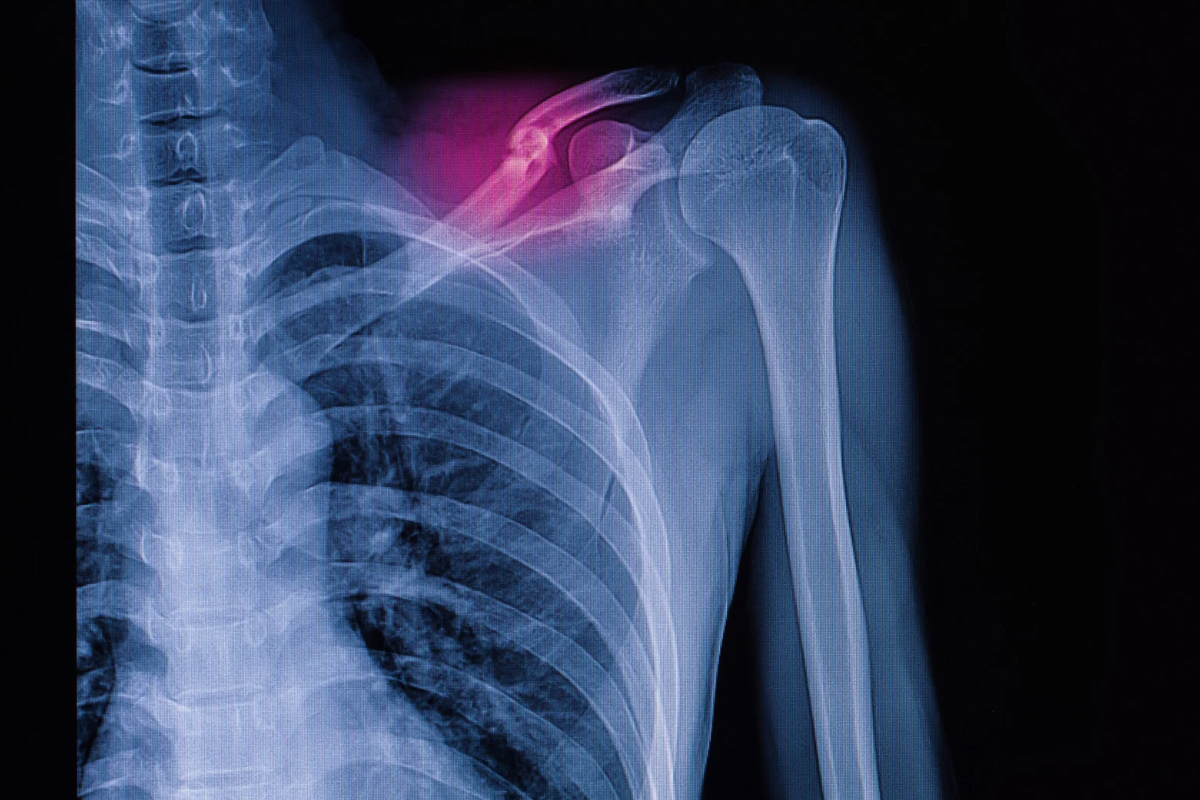

Durerile cronice de umeri sunt o problemă frecvent întâlnită, care poate fi cauzată de mai multe factori, inclusiv poziții incorecte, suprasolicitare sau afecțiuni precum tendinita, bursita sau artrita. Aceste dureri pot deveni debilitante, afectând activitățile zilnice, cum ar fi ridicarea brațului, ridicarea obiectelor sau chiar dormitul. Masajul medical și fizioterapia sunt soluții eficiente pentru reducerea durerii, îmbunătățirea mobilității și prevenirea recidivelor. La KinetikMed din Cluj-Napoca, specialiștii noștri folosesc tehnici avansate pentru a ajuta pacienții să scape de disconfortul cronic și să recâștige mobilitatea brațului și a umerilor.